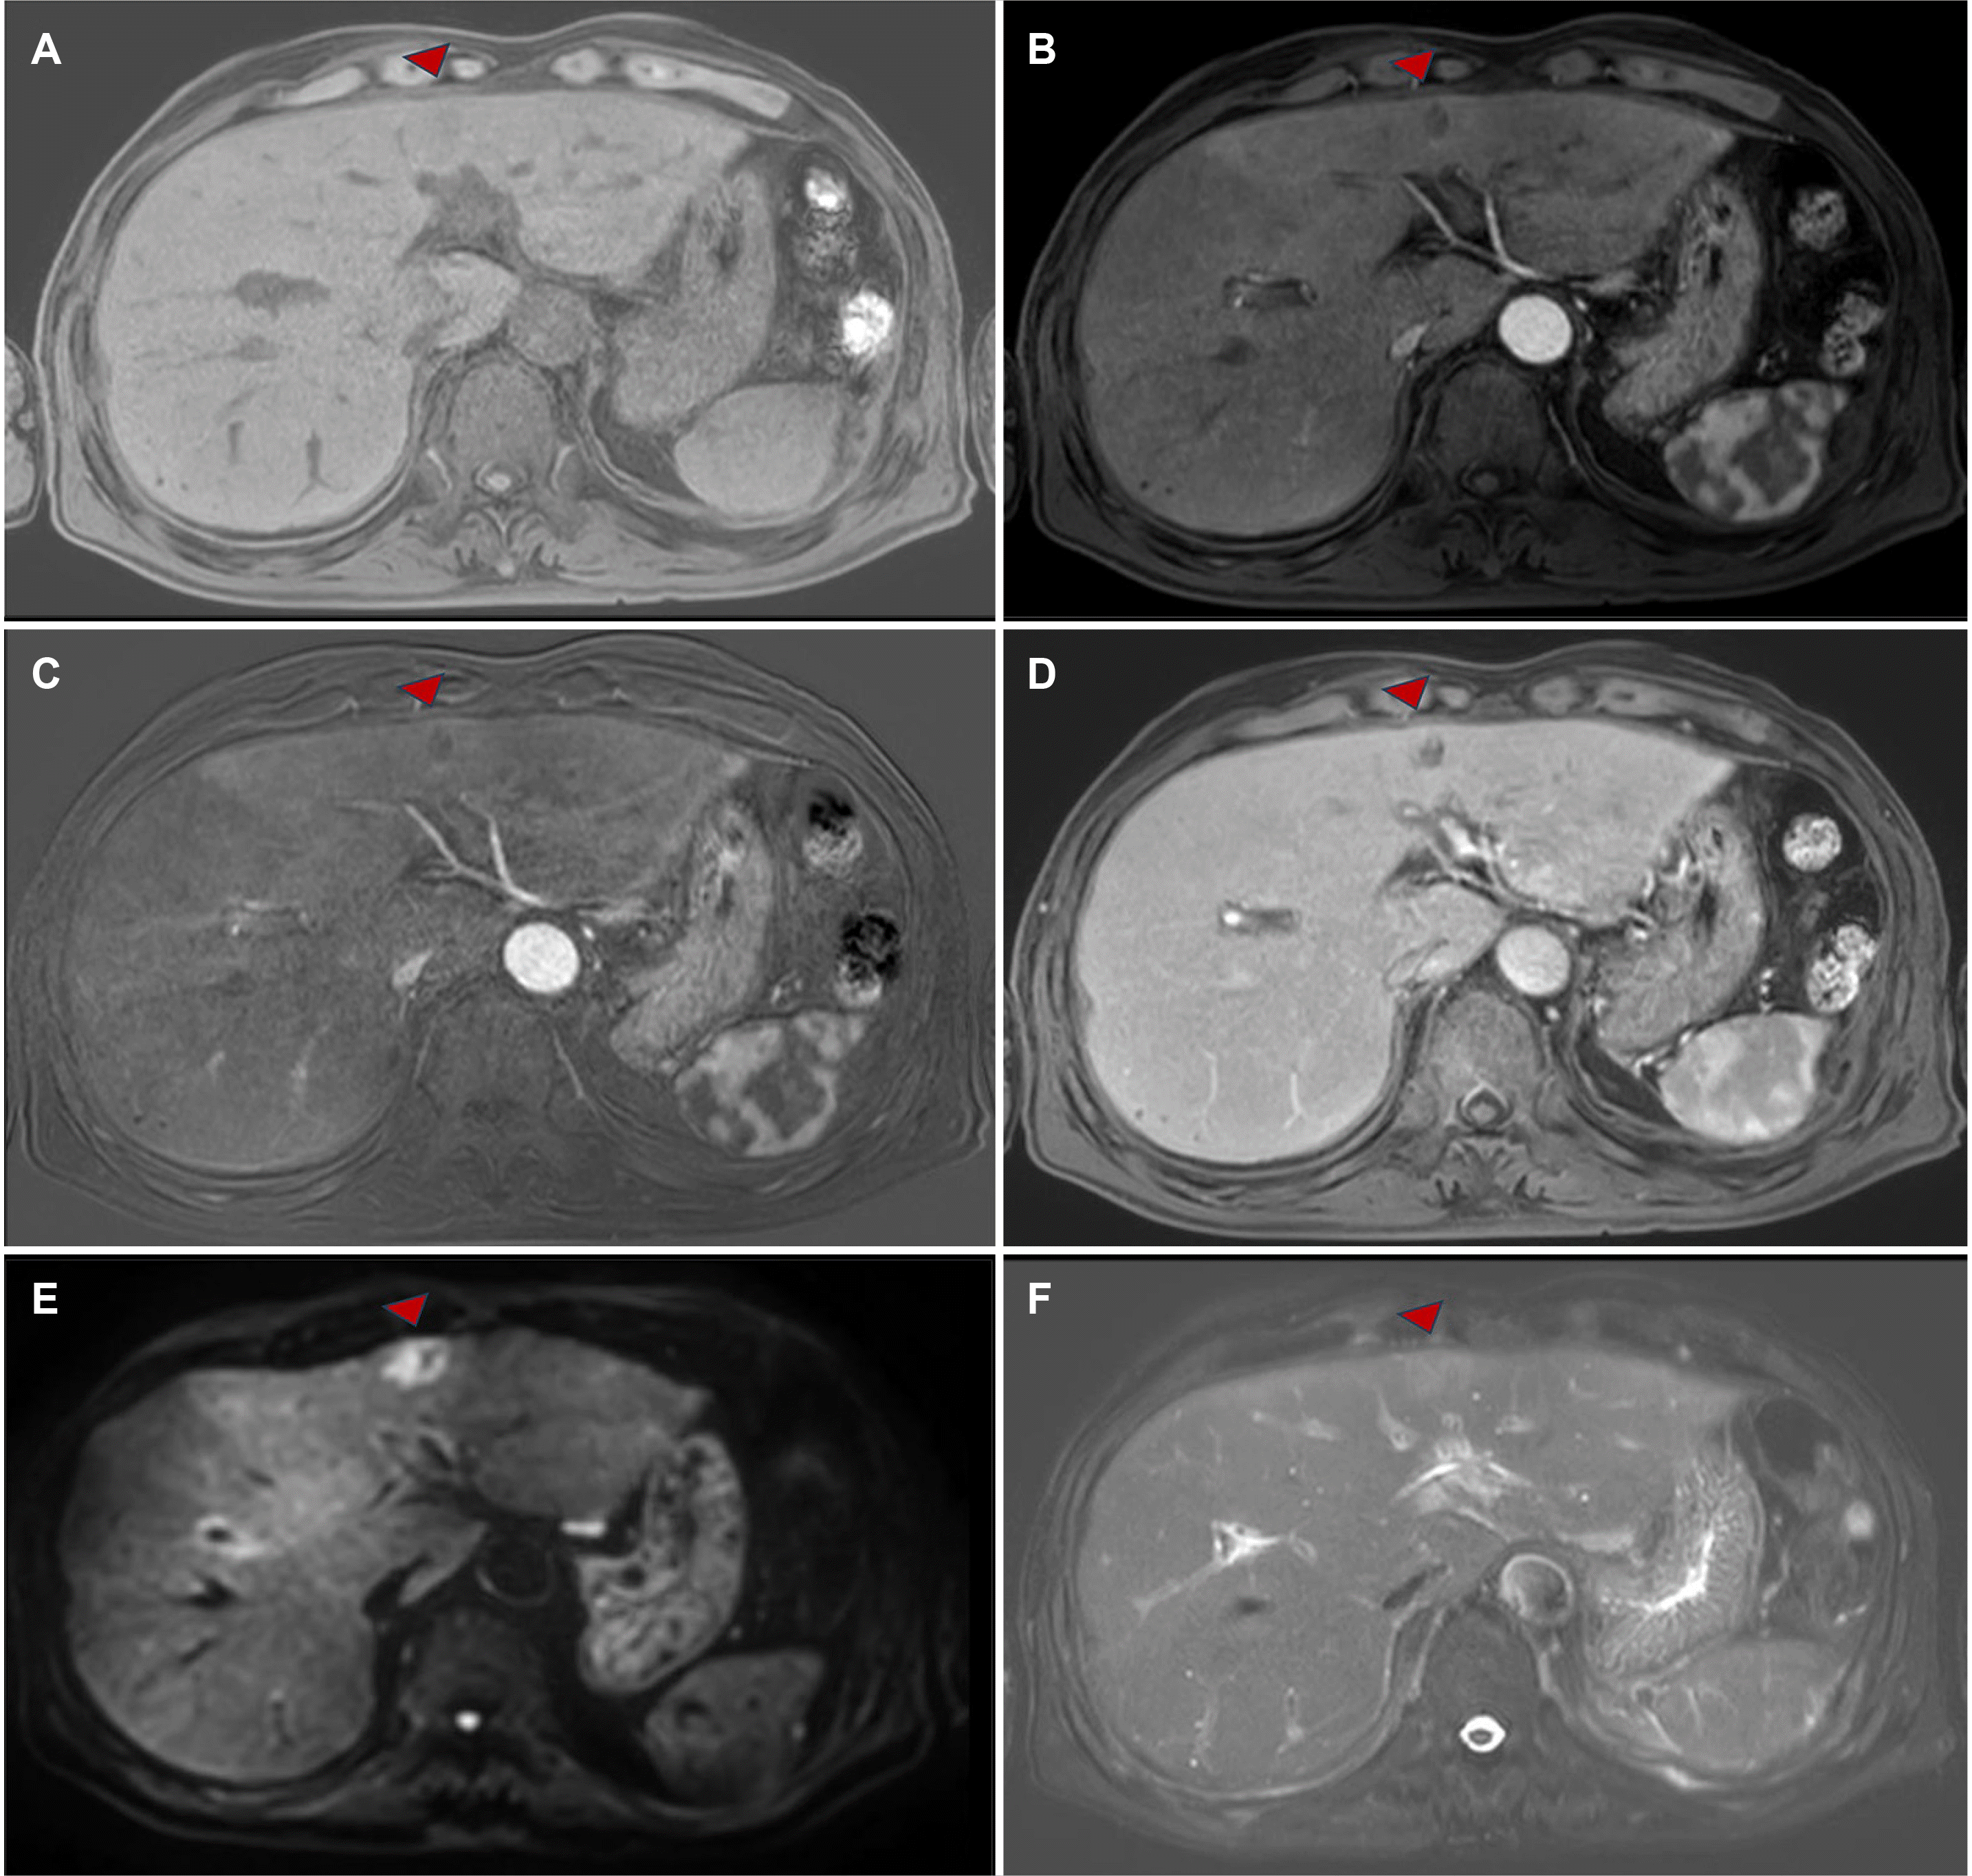

Upon examination, the patient's vital signs were found to be stable, with a body temperature of 36℃, a pulse rate of 102 beats/min, a respiratory rate of 18/min, and a blood pressure of 111/79 mmHg. Liver function tests demonstrated a cholestatic pattern with the following results: Aspartate aminotransferase level of 132 U/L, alanine transaminase level of 36 U/L, alkaline phosphatase (ALP) level of 501 U/L, and gamma-glutamyl transpeptidase level of 522 U/L. Abdominal CT demonstrated a 2.5 cm-sized heterogeneous nodule within S3/4 of the liver, exhibiting diffusion restriction but unclear margins prior to contrast enhancement. Furthermore, a 1 cm-sized low-density lesion was identified in S8 of the liver (Fig. 1).

These were initially diagnosed as benign lesions, suspected to be inflammatory liver abscesses. The patient was treated with an empiric regimen of piperacillin-tazobactam for one week. However, the patient's symptoms persisted. Follow-up imaging did not demonstrate any improvement (Fig. 2).

Fig. 2

Axial magnetic resonance imaging shows the corresponding lesion. (A) On T1-weighted imaging, a slightly hypodense mass is observed in S3/4 of the liver (red arrowhead). (B) Mild peripheral enhancement is seen in the arterial phase after contrast administration. (C) In the arterioportal phase, the lesion margins remain mildly enhanced, with no enhancement in the central portion. (D) In the portal venous phase, contrast enhancement is more prominent toward the center of the lesion from the peripheral rim. (E) On diffusion-weighted imaging, the suspected area of hepatic tuberculosis shows a high signal. (F) On T2-weighted imaging, the lesion demonstrates a mixed pattern of hyperintense and hypointense signals.